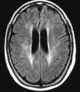

Whole brain radiation

Whole brain radiotherapy (WBRT) is a palliative option for patients with brain metastases that alleviates symptoms, decreases the use of corticosteroids needed to control tumor-associated edema, and potentially improves overall survival. It has been reported to increase the risk of cognitive decline. [Source: Wikipedia ]